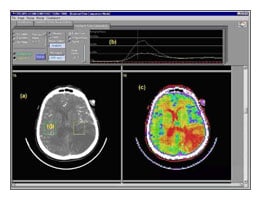

Soluções de alta tecnologia com baixo custo para a medicina. Essa é a proposta do Projeto Cyclops, uma colaboração binacional entre Alemanha e Brasil que, desde 1997, vem desenvolvendo projetos de suporte ao diagnóstico médico radiológico, através de pesquisas em áreas como banco de dados de imagens médicas, telemedicina e workflow médico-hospitalar. Para outubro, o Projeto Cyclops prepara a 4ª Edição do Simpósio Catarinense de Processamento de Imagens Médicas (SCDPI2004), que será realizado, entre os dias 18 e 20, na Universidade Federal de Santa Catarina (UFSC).

Todas as aplicações desenvolvidas pelo projeto Cyclops trabalham com padrões internacionais. Dentre eles, o mais comum é o Digital Imaging and Communication in Medicine (DICOM), amplamente utilizado em equipamentos de diagnóstico tradicionais, como máquinas de raio-x, ultrassonografia, ressonância magnética, tomografia computadorizada e medicina nuclear.

Na área de telemedicina, uma das tecnologias desenvolvidas é a sala de laudo virtual, que proporciona uma teleconferência radiológica. Nela, diversos médicos, a partir de seus computadores pessoais, participam de uma sessão de discussão, onde todos os movimentos de mouse nas imagens no computador de um dos participantes, como uso de lupas, marcações e medições de regiões, são visualizadas pelos demais médicos.